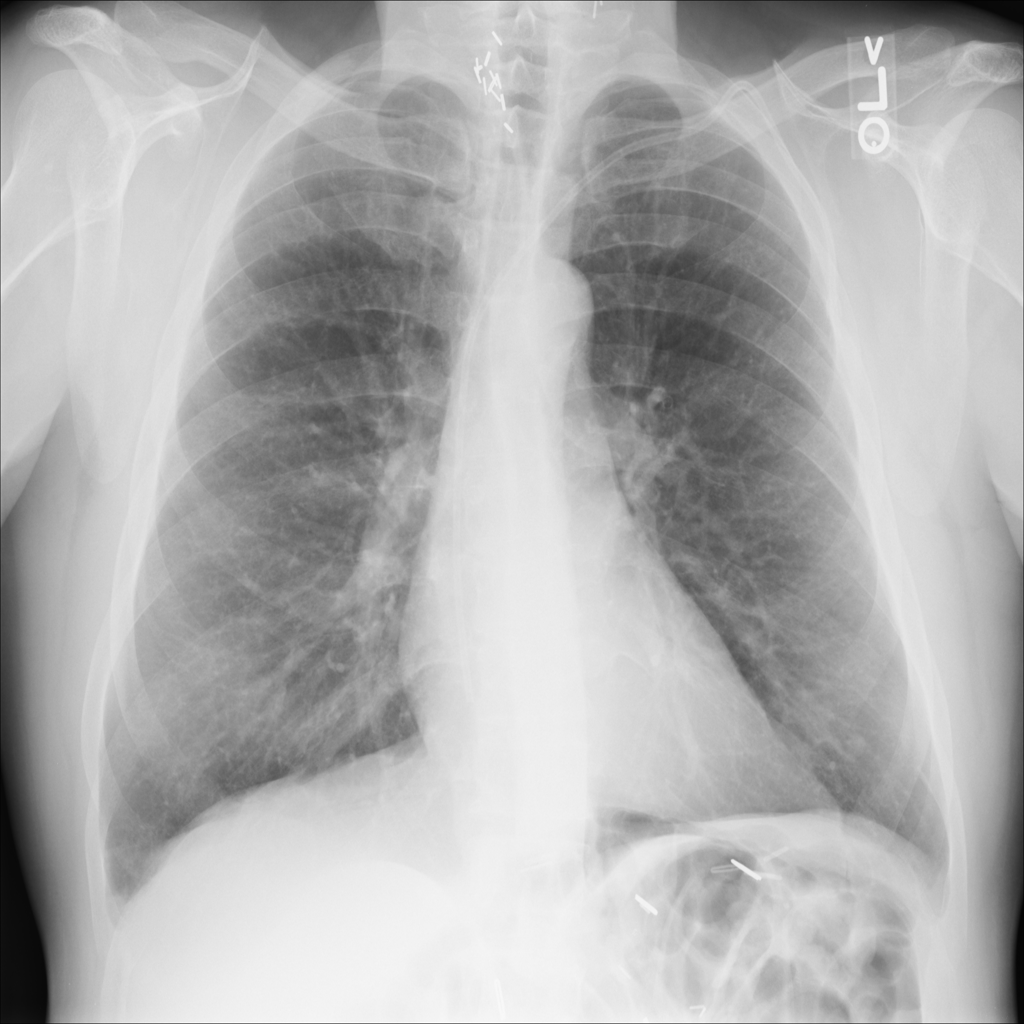

PAT-26A3 · IMG-008Nodule

PAT-26A3 · IMG-008

AP